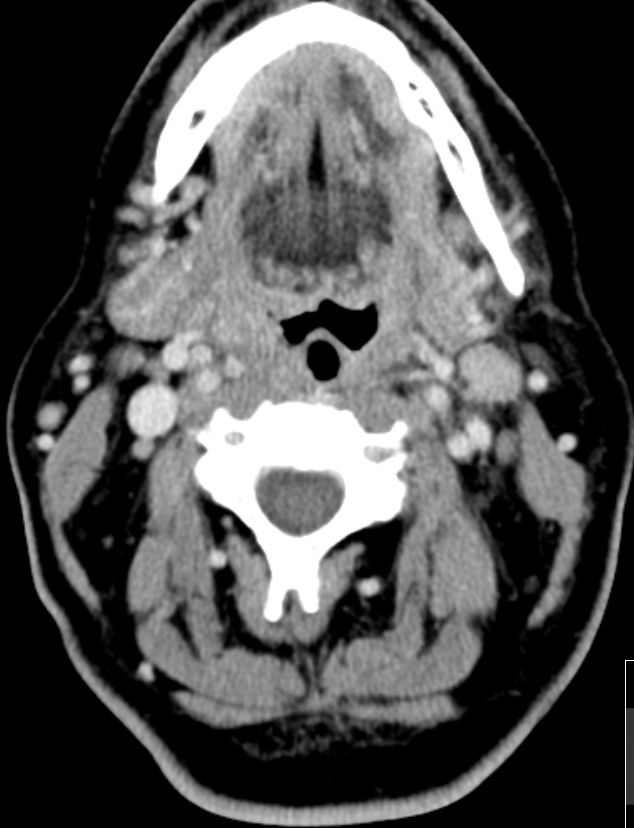

Hals |

55-jähriger Mann mit zervikalem

links am Vorderrand des M. sternocleidomastoideus. Histologie:

Marginalzonenlymphom. Klinik: keine Symptome, Labor, Staging-CT, Knochenmark

o.B.![]() | ||